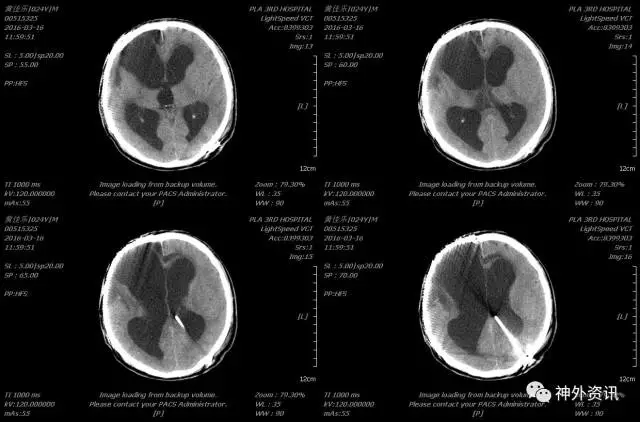

2015-12-02 12:33 伤后1小时我院急诊科复查头颅CT(2015-12-02 12:33):

入科后急诊在全麻下行去骨瓣减压及硬膜下血肿清除术,植入脑实质内颅内压监测,术后患者颅内压正常范围,生命体征平稳,术后第二日复查头颅CT及胸部CT(术后约14小时,2015-12-03 09:33):

患者术后虽然颅内显示正常,但挫伤出血量大,脑肿胀明显,行二次开颅颅内血肿清除术,术后复查头颅示(2015-12-04 09:05):

术后给予镇痛、镇静、机械通气、脱水、止血、抗感染、目标性体温控制、营养支持等治疗,术后4天复查头颅CT及胸部CT示(2016-12-08 10:39):